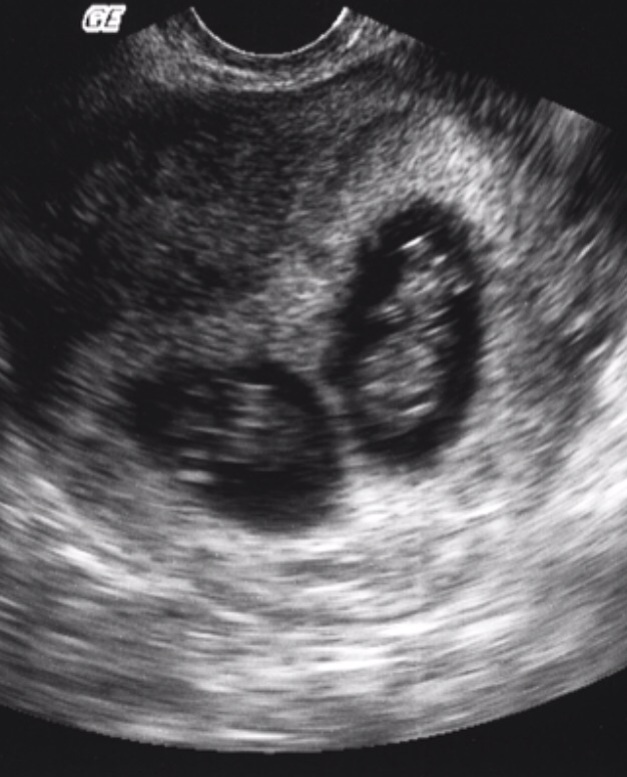

Hi everyone! I was holding back on posting anything on here and have been admiring everyone's stories for the past month until I can get in for my first ultrasound. I'm 9 weeks 4 days today.....and just found out we're having twins!! We're scared but excited and up for the challenge!

We've been trying for a baby for over a year and had to go in clomid. We decided third round would be our last.....and that's the one that worked! You can imagine our shock when the Dr told my husband "you may want to sit down".

Here's a little good night picture to all you mommas!!! Post your pictures :)